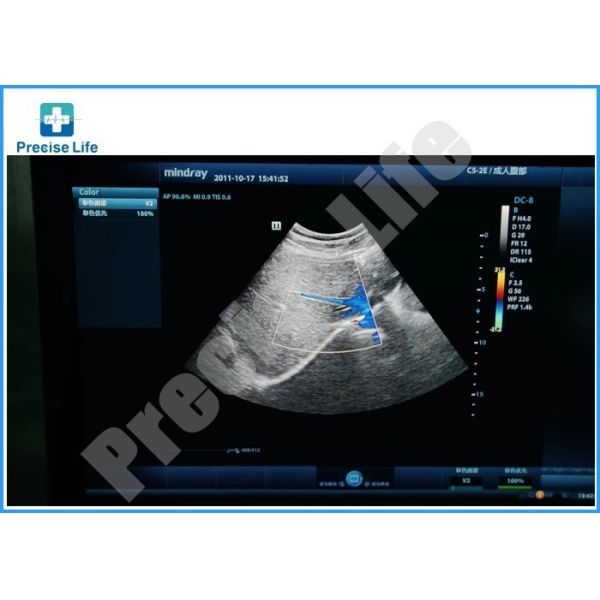

Mindray C5-2E Ultrasound Probe Convex Transducer For DC 8 Machine

Compatible Mindray C5-2E ultrasound probe Convex array C5-2E ultrasonic transducer replacment

The Mindray C5-2E convex ultrasound transducer is designed for adult abdominal, pediatric abdominal, OB/GYN, vascular and nerve imaging applications. The C5-2E probe is compatible with the Mindray DC-70, DC-8 and DC-8 Expert console ultrasound machines.

| Image quality | Up to 90%~95% compare to original |

Replacement ultrasound probe with high quality compare to original image up to 90%~95%,but with reasonable cost about 20%~30% compare to original.